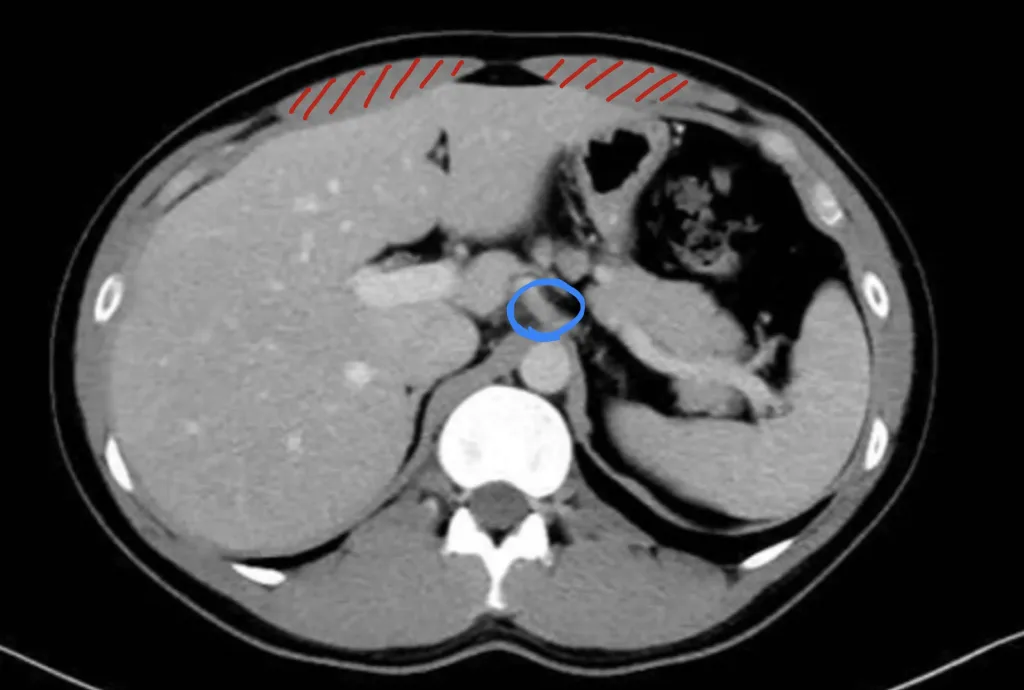

上の図は腹腔神経叢のレベル(みぞおちの位置)のCT画像です。CT画像の見方については、仰向けの人を輪切りにして、足元側から見ているのをイメージしてください。つまり、画像の上が腹側、下が背側、画像左が身体の右側、画像の右が身体の左側となります。この図の青丸が腹腔神経叢の位置です。筋肉は赤の斜線で示しており、こちらは腹直筋になります。骨は白色に映ります。この場合、腹腔神経叢を守るものとして腹直筋(赤い斜線)があるのですが、身体の中心は腹直筋の腱(スジみたいなもの)で構成されており、ここはいくら筋トレをしても太くなりません。つまり腹腔神経叢を守るために腹直筋を肥大させることはあまり意味がないと考えられます。次に肝臓について考えてみましょう。